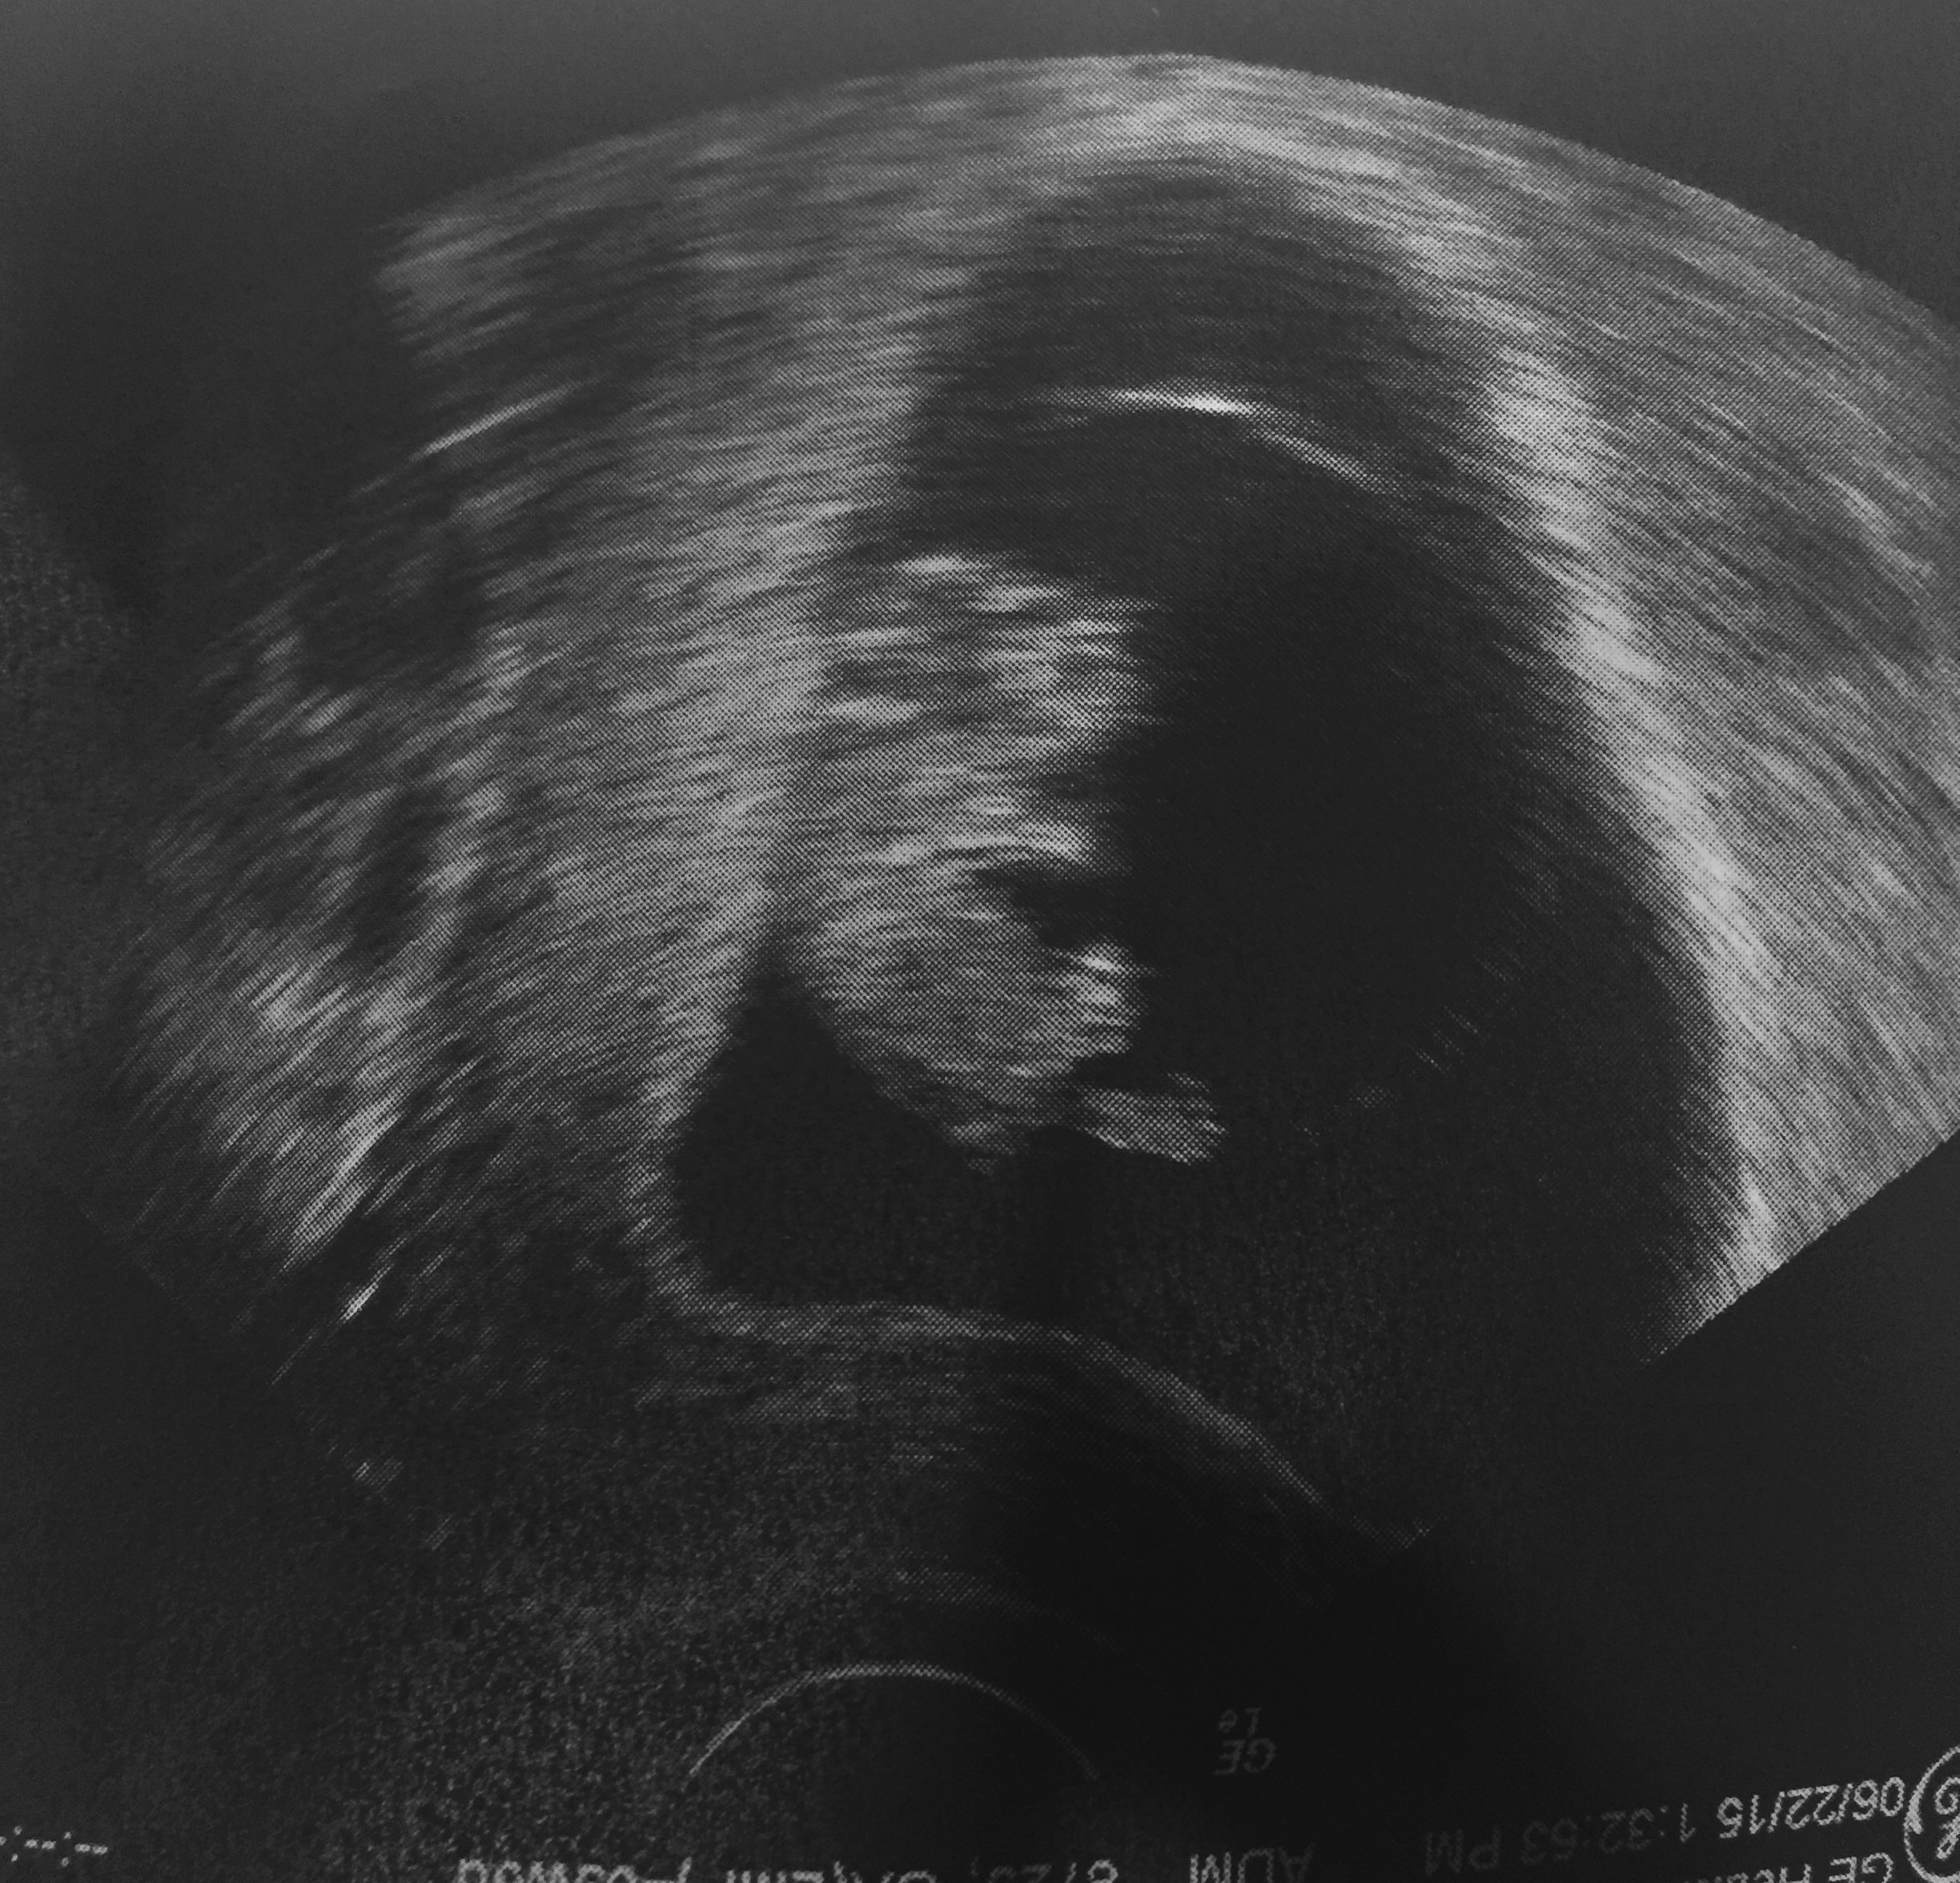

saw peanut today at just 10wks and ohh my was he or she happy to be seen(: waving and kicking very active baby with a HR if 170!